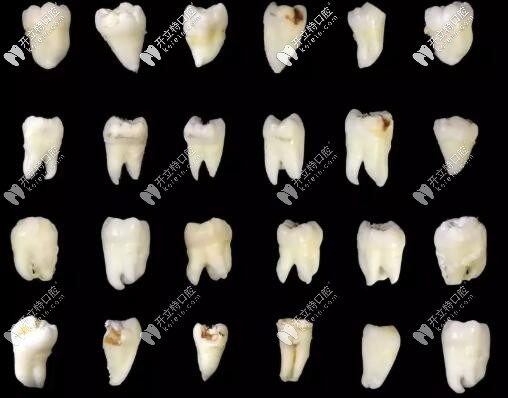

智齒的各種形態(tài)

這是某位醫(yī)生拔過(guò)的智齒